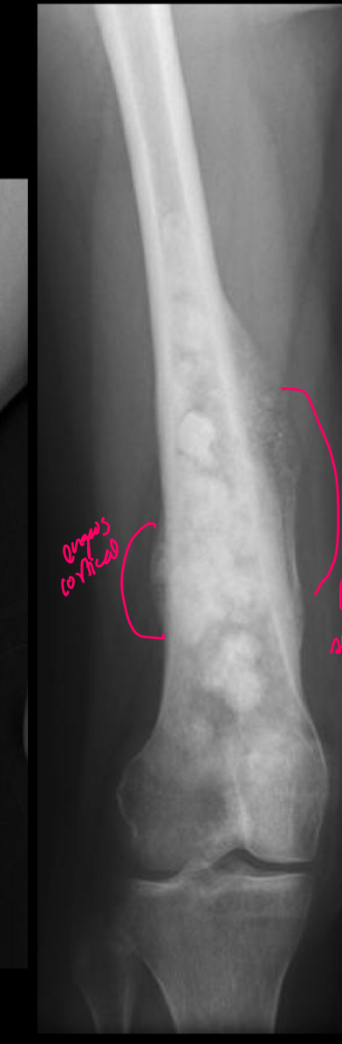

11

Q

q se ve q tiene

A

Engrosamiento de la cortical

Reac periostica: como q se levanta el periostico

Triangulo de codman